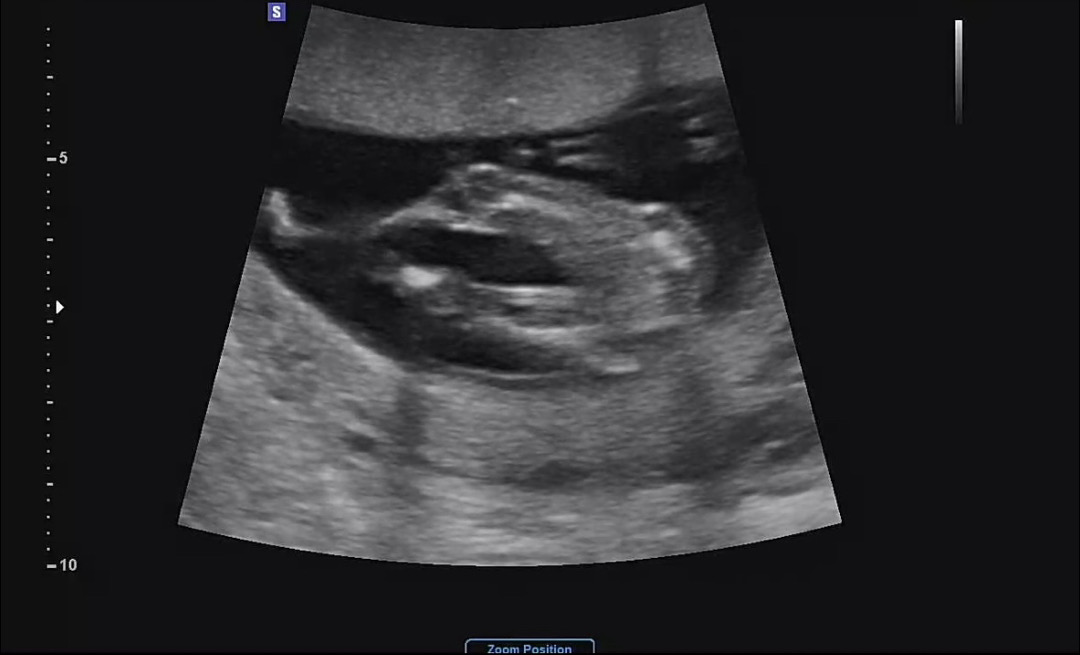

14주차 반전이없을까요?

딸이라고 얘기를 듣기했는데 혹시 반전은 없겠죠? ㅎㅎ

없울고 같애요 너무 확실하게 튀어나온게 없네요 ㅎㅎㅎㅎ.......😢